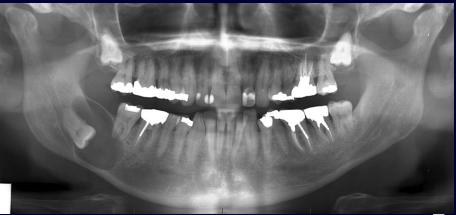

What are the different types of artifact available on CBCT?

A

1.Beam hardening – streaks arising from very dense objects

2.Scatter – soft streaking

3.Motion – blurry or double vision

4.Poor machine care – multiple artifacts

5.Faulty detector – rind around the jaw